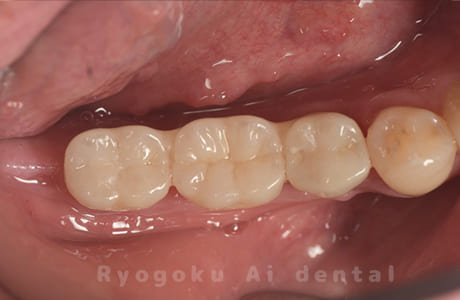

Case10

-

術前

術後

- 原因

- 左下6番欠損

- 治療内容

- インプラント治療

- 治療費用

- 約600,000円

左下の奥歯に歯を入れて欲しいとのことでご来院された患者様です。インプラント治療が最適とご提案させて頂き、治療を行いました。経過も良好で、大変満足して頂けました。

<リスク・副作用>

治療後、痛みや違和感、出血、腫れなどが出る事があります。喫煙者、糖尿病などの方の場合、歯が生着しない場合があります。